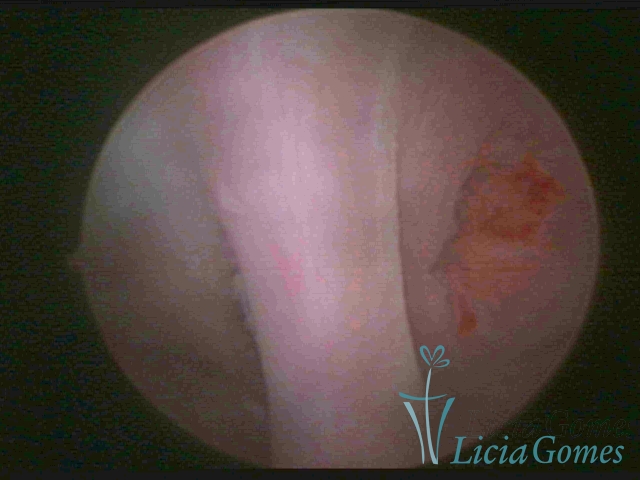

Bicornuate uterus

Malformation in which there is the lack of the flat portion of uterine fundus due to the lack of fusion on the proximal portion of paramesonephric ducts. The uterine fundus has two narrowed spaces in a divergent oblique angulation. It may be complete, from the fundus to the cervix; or partial, completely dividing the uterine cavity.

The tilted uterus which presents the most difficult hysteroscopic diagnosis occurs when there is only a small indentation of the uterine fundus.